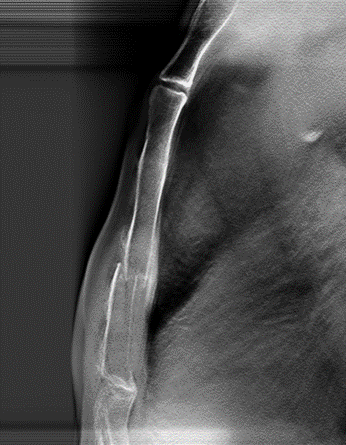

病例五:男,37岁。胸部外伤。

断层融合能够清晰显示肋骨骨折。